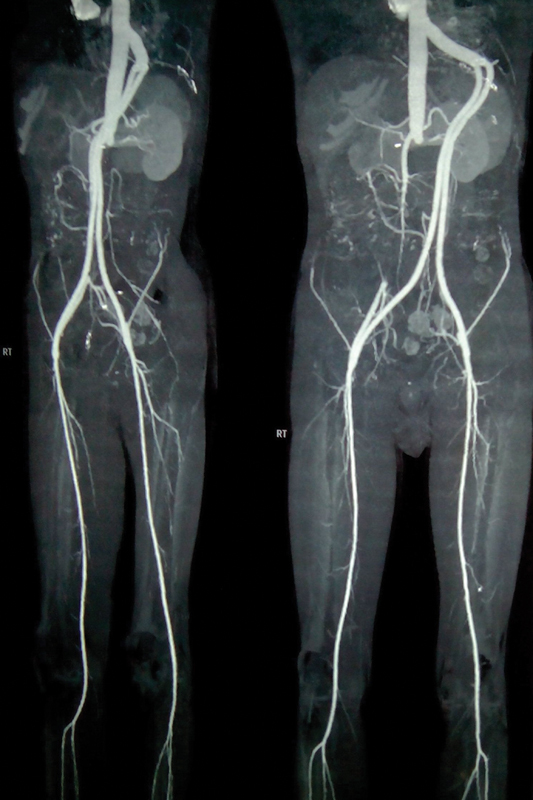

Thoracofemoral bypass is primarily utilized as a secondary intervention for juxtarenal aortoiliac occlusive disease, with limited instances of its application as an initial treatment, leading to uncertain long-term outcomes. This analysis aims to scrutinize the 10-year experience and early outcomes of 90 patients who underwent thoracofemoral bypass as a primary procedure.A retrospective analysis was conducted on patients undergoing thoracofemoral bypass for severe aortoiliac occlusive disease between August 2012 and August 2022. The primary indication was complete abdominal aorta obstruction at the renal artery level with an unsuitable site for aorta clamping. The BARD IMPRA expanded polytetrafluoroethylene vascular graft was employed for thoracobifemoral bypass surgery.Among the 90 patients, 83 (92.22%) were male, and 7 (7.78%) were female, with ages ranging from 51 to 77 years. Intraoperative and postoperative data were analyzed, and the mean follow-up duration was 30 days. The 30-day mortality rate was 3.33% (n = 3). Major morbidities included graft occlusion in one patient, managed by embolectomy, and ascites in another patient, addressed conservatively.This study demonstrates that thoracic aorta to femoral artery bypass, as a simple extra-anatomic bypass technique, can yield favorable outcomes when chosen as the initial treatment for patients with juxtarenal total aortoiliac occlusive disease. Thoracofemoral bypass exhibits a safe, acceptable outcome with reliable patency.

Abstract Image